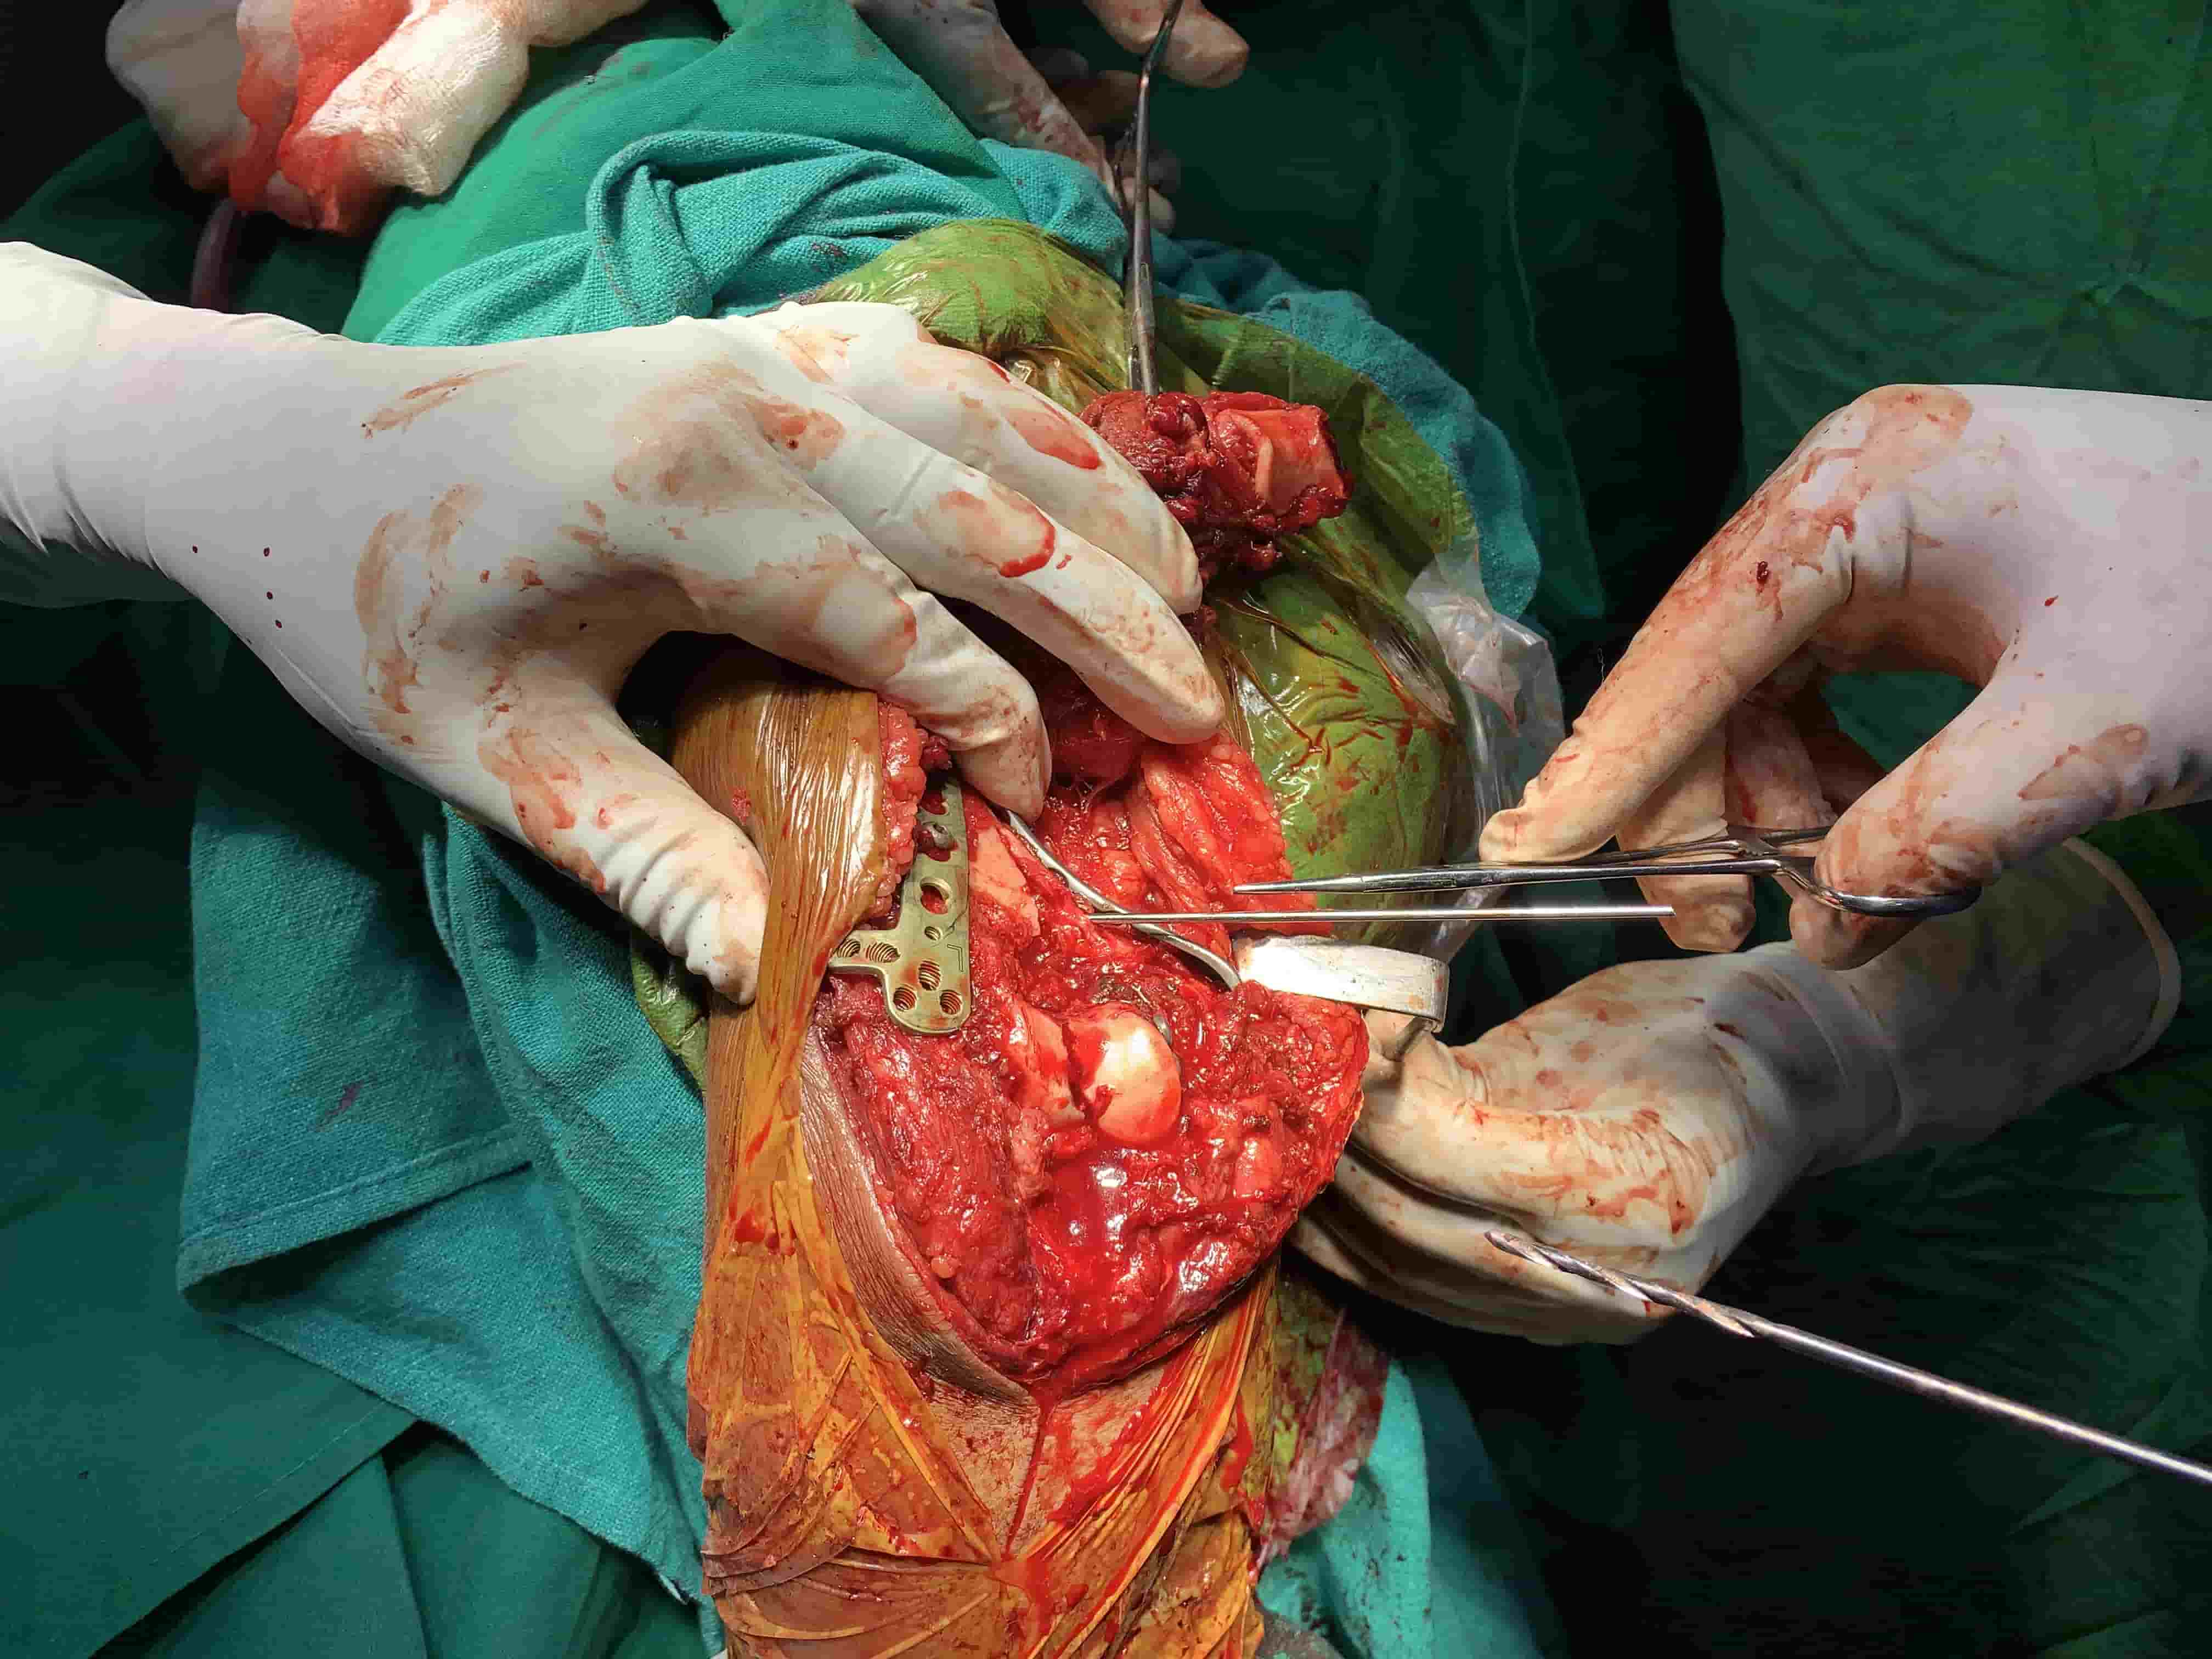

Complex Distal Humerus Comminuted Fracture

Complex Distal Humerus Comminuted Fracture

Complex Distal Humerus Comminuted Fracture

Complex Distal Humerus Comminuted Fracture

Complex Distal Humerus Comminuted Fracture

Complex Distal Humerus Comminuted Fracture

Complex Distal Humerus Comminuted Fracture

Complex Distal Humerus Comminuted Fracture

Complex Distal Humerus Comminuted Fracture

Complex Distal Humerus Comminuted Fracture

Complex Distal Humerus Comminuted Fracture

Complex Distal Humerus Comminuted Fracture

Complex Distal Humerus Comminuted Fracture

Complex Distal Humerus Comminuted Fracture